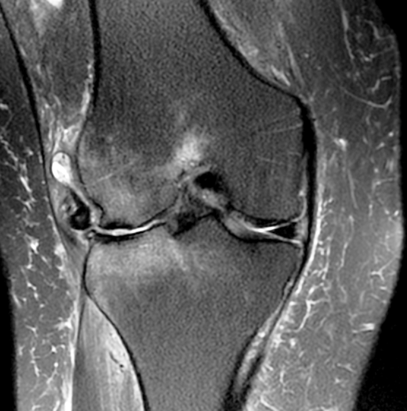

2. RMN

Útil para avaliar cartilagem, meniscos e estruturas associadas.